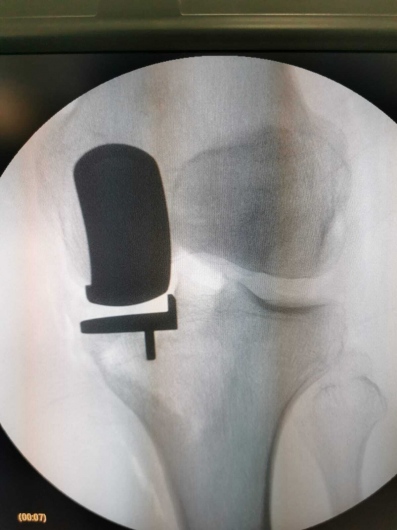

Fotos y videos